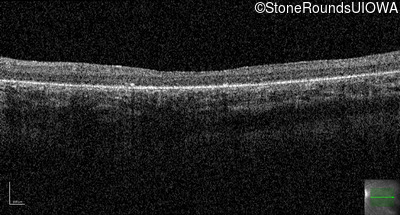

Age at visit: 11 years